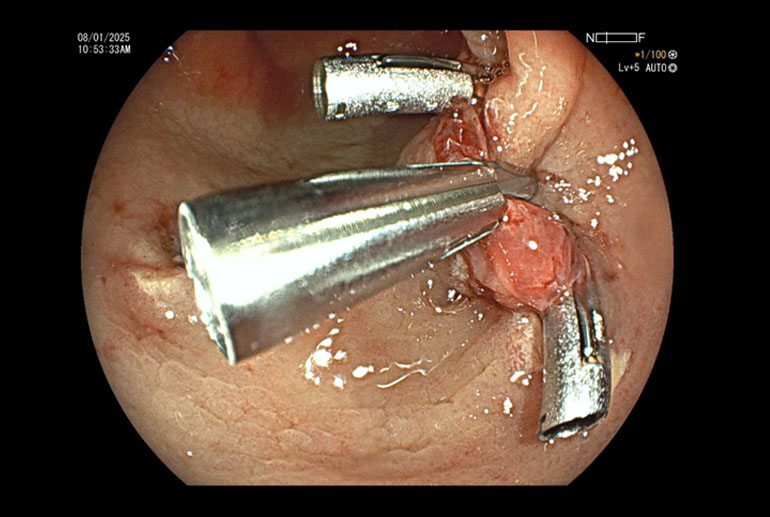

Our patient had multiple polyps ranging between 7mm to 15 mm. Most of the polyps were flat, classified as Paris to AA. Several of these polyps were situated in cecum and ascending colon where colonic wall is quite thin and risk of perforation is higher. Using the technique of hydraulic immersion, it was possible to remove all these polyps with minimal risk to the patient. Post polypectomy site of the largest removed polyp was seen to be oozing blood; this was sealed with application of 3 hemoclips; effective hemostasis was achieved and patient did not suffer any complications.